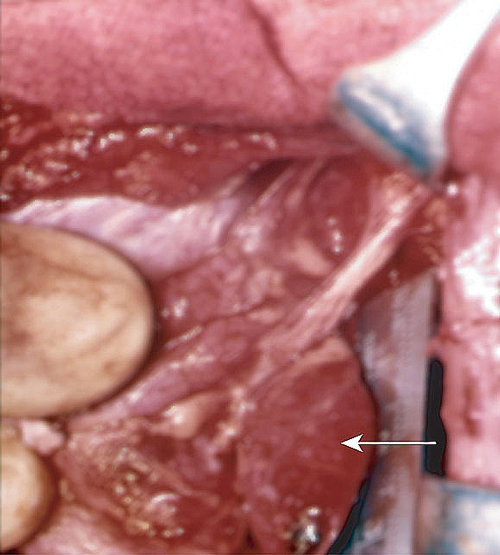

5: Case report — investigating hypercalcaemia

A single parathyroid nodule (arrow) is found at surgery in 85% of cases of hyperparathyroidism. Single nodules are unlikely to recur. Remaining cases are due to hyperplasia of more than one gland, which often recurs.